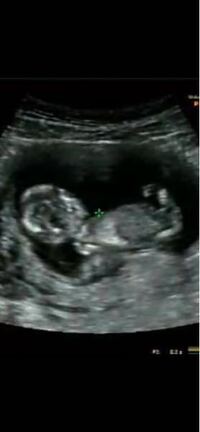

子どもの性別 いつわかる? 妊娠初期〜12週頃までは、経膣超音波検査、それ以降は経腹超音波検査となることが多いですが、施設によって違いがあります。 赤ちゃんの性別は、妊娠4か月頃(妊娠12〜15週頃)にはわかることもあります。5ケ月でわかるというのですが、 どうも検診のたびに足で隠したり胎盤が邪魔だったり、 エコーでは見えない背中側に向いてしまってみえなかったりの連続の為、 先週やっとわかったといった 早い時期ですと、妊娠16週ごろに性別が判明したケースが多いようです。ちょうど安定期に入る時期で、ママに心の余裕が出るころでもありますね。 妊娠18週 シンボルが見えた 妊娠18週(5ヶ月)に性別がわかりました。健診の際に医師から「性別知りたい?

はっきりわかるのは、 赤ちゃんが600~1000グラムになる妊娠24週目(妊娠7ヶ月)以降 といわれています。 性別を間違えることはある? 男の子としては判定されるのは、 股の部分にピーナッツのような突起物として陰茎がエコーに映った場合 です。赤ちゃんの性別はいつわかる?まとめ 赤ちゃんの性別が分かるのには個人差があります。 赤ちゃんの性別はいつわかるの?というと、 早い人だと4ヵ月ごろにわかったひとも。 ほとんどは妊娠5~7ヵ月にわかることが多いようです。一般的には、妊娠18~週くらいから判定できることが最も多く、21週を過ぎるとさらに判別がつきやすくなります。 早い人では12~14週 で分かる人もいるそうですよ。 時期が来たら判別できると分かっていても、性別はやっぱり気になるものですよね?

妊娠したら性別っていつ分かるの? こんにちは、ゆにっき!です。 妊娠してだんだん妊婦さんの自覚が出てきたくらいの時期って、赤ちゃんの性別が気になる時期でもありますよね。 性別はいつ頃判明するものなのでしょうか。 大体17~25週ごろが平均 妊娠中、赤ちゃんの性別がわからなかった! ドキドキのエコー検査! 「次の検診くらいに赤ちゃんの性別わかるかな」 お医者さんから告げられて、とってもドキドキしました。 でも、安定期に入ってからの検診は、約2週間に1度になるんです。 妊娠7~12週頃には、泌尿器(排尿する部分)と直腸や肛門(排便する部分)のかたちが作られます。妊娠16週を過ぎたころから、外性器の見た目で性別を判断できるようになります。 目次 ・赤ちゃんの性別はいつ決まる? ・赤ちゃんの性別はいつわかる?

胎児の性別はいつわかる? 結論からいうと、私は妊娠5ヶ月(19週)で確定となりましたが、一般的に赤ちゃんの性別はいつ分かるのでしょうか? 赤ちゃんの性別は、アプリ「トツキトオカ」の赤ちゃんも言っている通り、 受精の瞬間に決まって います。 お笑い芸人 岡村隆史の子共の性別と誕生日は? いつ産まれたの? 岡村隆史さんの結婚相手はバレリーナをされていた方です。 お嫁さんの年齢は、岡村隆史さんよりも12歳年下なので 39歳です。 誰なのか詳しい情報は非公開になっています。 実家は 胎児の性別がわかる時期 赤ちゃんの性別がわかる時期は妊婦や胎児によって個人差があります。 ですが、妊娠中期頃にわかる場合が多いと言われています。(妊娠中期:妊娠5ヶ月「16周」〜妊娠7ヶ月「27週」) 性別の判明は、男女によっても少し差があり